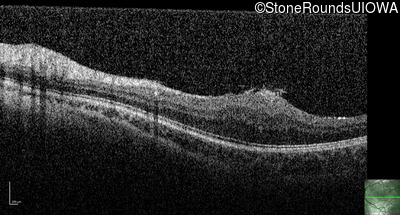

Optical Coherence Tomography - Right - 20/2000

Exemplar / OCT Stack